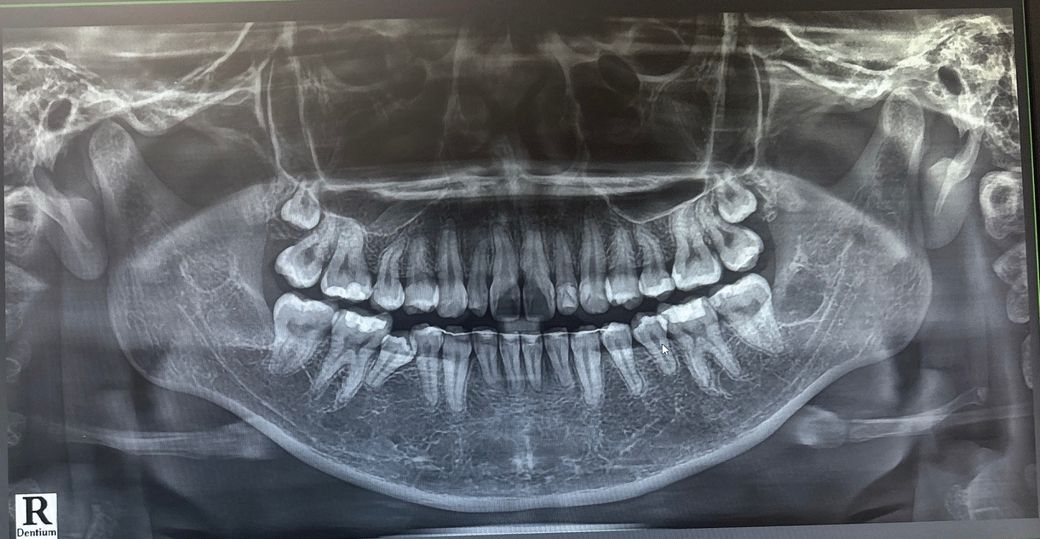

(사진O) 화질이 안 좋긴한대 파노라마 사진상 치아 전반적으로 문제 있는게 있을까요??

화질이 안 좋긴한대 파노라마 사진상 치아 전반적으로 문제 있는게 있을까요??

화질이 안 좋긴한대 파노라마 사진상 치아 전반적으로 문제 있는게 있을까요?? -> 특별히 큰 문제 없어보입니다

파노라마 상으로는 크게 문제가 없어 보이고, 치료를 많이 받으신거 같으니 관리를 잘하시는게 중요할것같습니다.

사진으로 보았을때는 좌측 맨 뒤의 치아에 인접면 사이의 충치로 보여지며 우측 작은 어금니 역시 침하되어 정상적인 교합이 아닐 가능성이 있어 보입니다. 다만 현재 사진은 전체적인 치아 상태를 보는 것이며 충치 및 정확한 판단을 위해서는 치과 방문 후 치아마다 사진을 찍어봐야 알 수 있습니다.

치아 뿌리가 짧아 보이는 부분이 몇군데 보입니다. 관리를 잘 해주셔야 할 것으로 보입니다.

사진으로 봤을 경우에는 크게 문제가 보이진 않습니다. 치료를 한 치아 주변에 부분적으로 검은색 음영이 보이는 걸로 보여 해당 부위에 충치가 있을 가능성은 있습니다.

자세한 확인을 위해서 치과에서 진료를 받아보는 것을 권유드립니다.